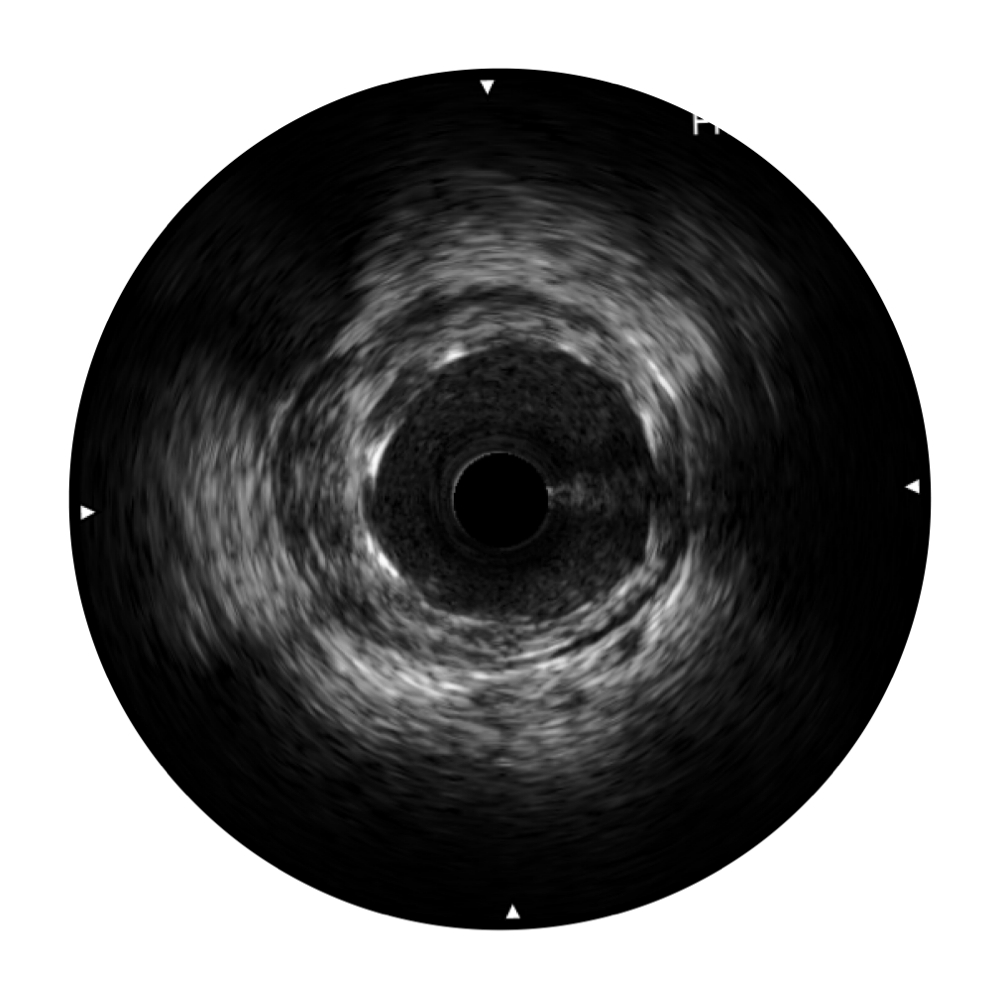

• 传统IVUS图像

对比传统IVUS导管成像,1xBET宽频IVUS图像的近场支架梁显影更细腻,远场中膜外血管仍清晰可辨,兼顾远中近,兼顾分辨力与穿透深度